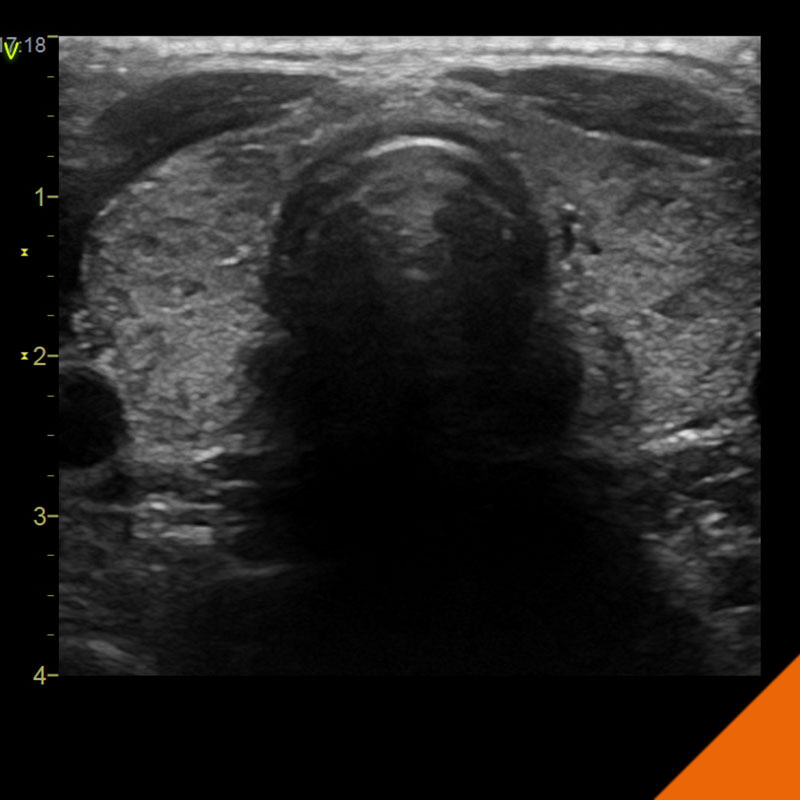

Herzinsuffizienz

Patienten mit Herzschwäche

...benötigen eine besondere Betreuung

Seit mehr als 20 Jahren widmen wir uns in unserer Praxis und in der klinischen Forschung der Früherkennung und Behandlung der Herzschwäche.

Nachfolgend erfahren Sie mehr über diese schwere und im höheren Alter zunehmend häufige Erkrankung, die enormen jüngsten Fortschritte bei der Behandlung, aber auch die Herausforderungen für Patienten, Angehörige und Behandlungsteams.